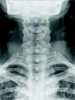

Neck trauma

A gunshot wound (GSW) is physical trauma caused by a bullet from a firearm. Damage may include bleeding, broken bones, organ damage, infection of the wound, or loss of the ability to move part of the body. [Source: Wikipedia ]